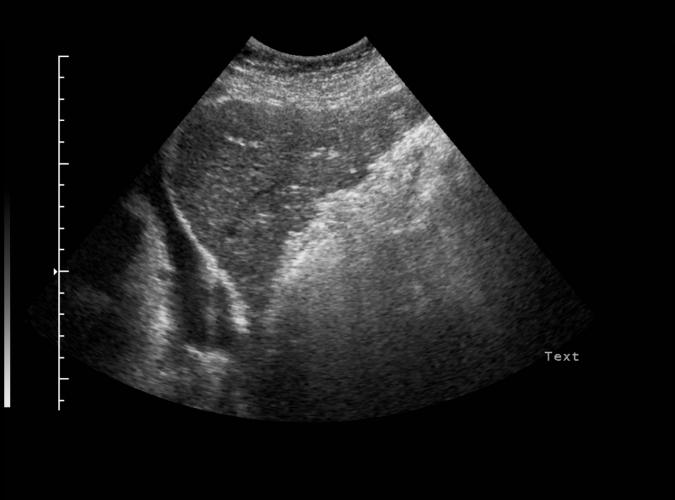

av Catherine Olsson, sonograf

Patologi.

Long. Lågekogen, skrumpen vänster leverlob med oregelbundna kanter. Bild som med resten av leverbilder 3b,c,d.talar för biliär cirrhos

Catherine Olsson, sonograf